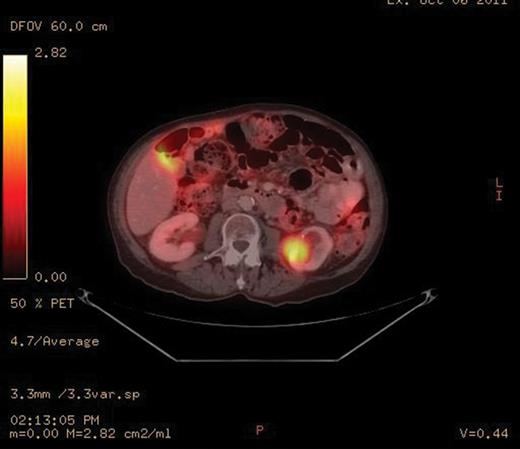

A PET-CT was performed, which demonstrated a round enhancing 1.8 × 1.5 cm right subpectoral lymph node with FDG uptake and a maximum SUV of 4.0 suspicious for metastatic disease (Figs 1 and 2). Additionally, an incidental 4.1 × 3.4 cm mass within the midpole of the left kidney was heterogeneously enhancing with increased FDG uptake and a maximum SUV of 8.6 suspicious for a renal cell carcinoma or less likely a transitional cell carcinoma (Figs 3 and 4).